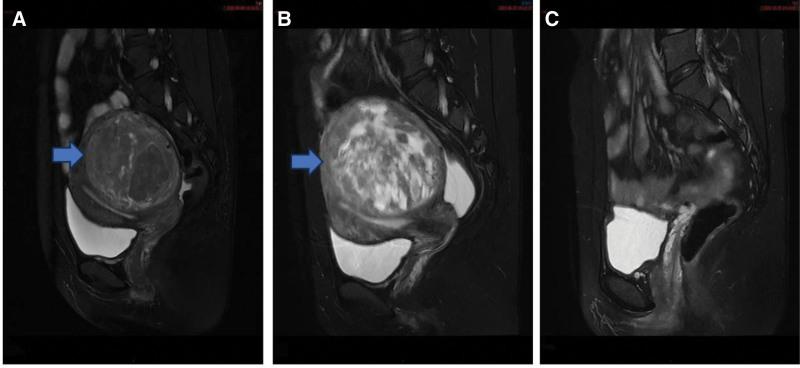

Two years ago, the patient underwent a single-port gasless laparoscopic myomectomy for uterine fibroids. Gynecological color Doppler ultrasound conducted 3 months ago revealed recurrence of uterine fibroids, and the patient experienced abdominal distension, mild urinary frequency, and constipation for the past month.

After the second surgical procedure, a comprehensive pathological examination and immunohistochemical analysis of both the uterine mass and metastatic lesions revealed that the definitive diagnosis was CLs.

患者 2 年前因子宫肌瘤行单孔非气腹腔镜子宫肌瘤剔除术。3 个月前妇科彩色多普勒超声发现子宫肌瘤复发,近 1 个月来出现腹胀、轻度尿频和便秘。

第二次手术后,对子宫肿块和转移灶进行全面的病理检查和免疫组织化学分析,明确诊断为 CL。